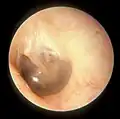

Right eardrum as seen through a speculum

In the anatomy of humans and various other tetrapods, the eardrum, also called the tympanic membrane or myringa, is a thin, cone-shaped membrane that separates the external ear from the middle ear. Its function is to transmit sound from the air to the ossicles inside the middle ear, and then to the oval window in the fluid-filled cochlea. Hence, it ultimately converts and amplifies vibration in the air to vibration in cochlear fluid.[1] The malleus bone bridges the gap between the eardrum and the other ossicles.[2]

When the eardrum is illuminated during a medical examination, a cone of light radiates from the tip of the malleus to the periphery in the anteroinferior quadrant, this is what is known clinically as 5 o'clock.